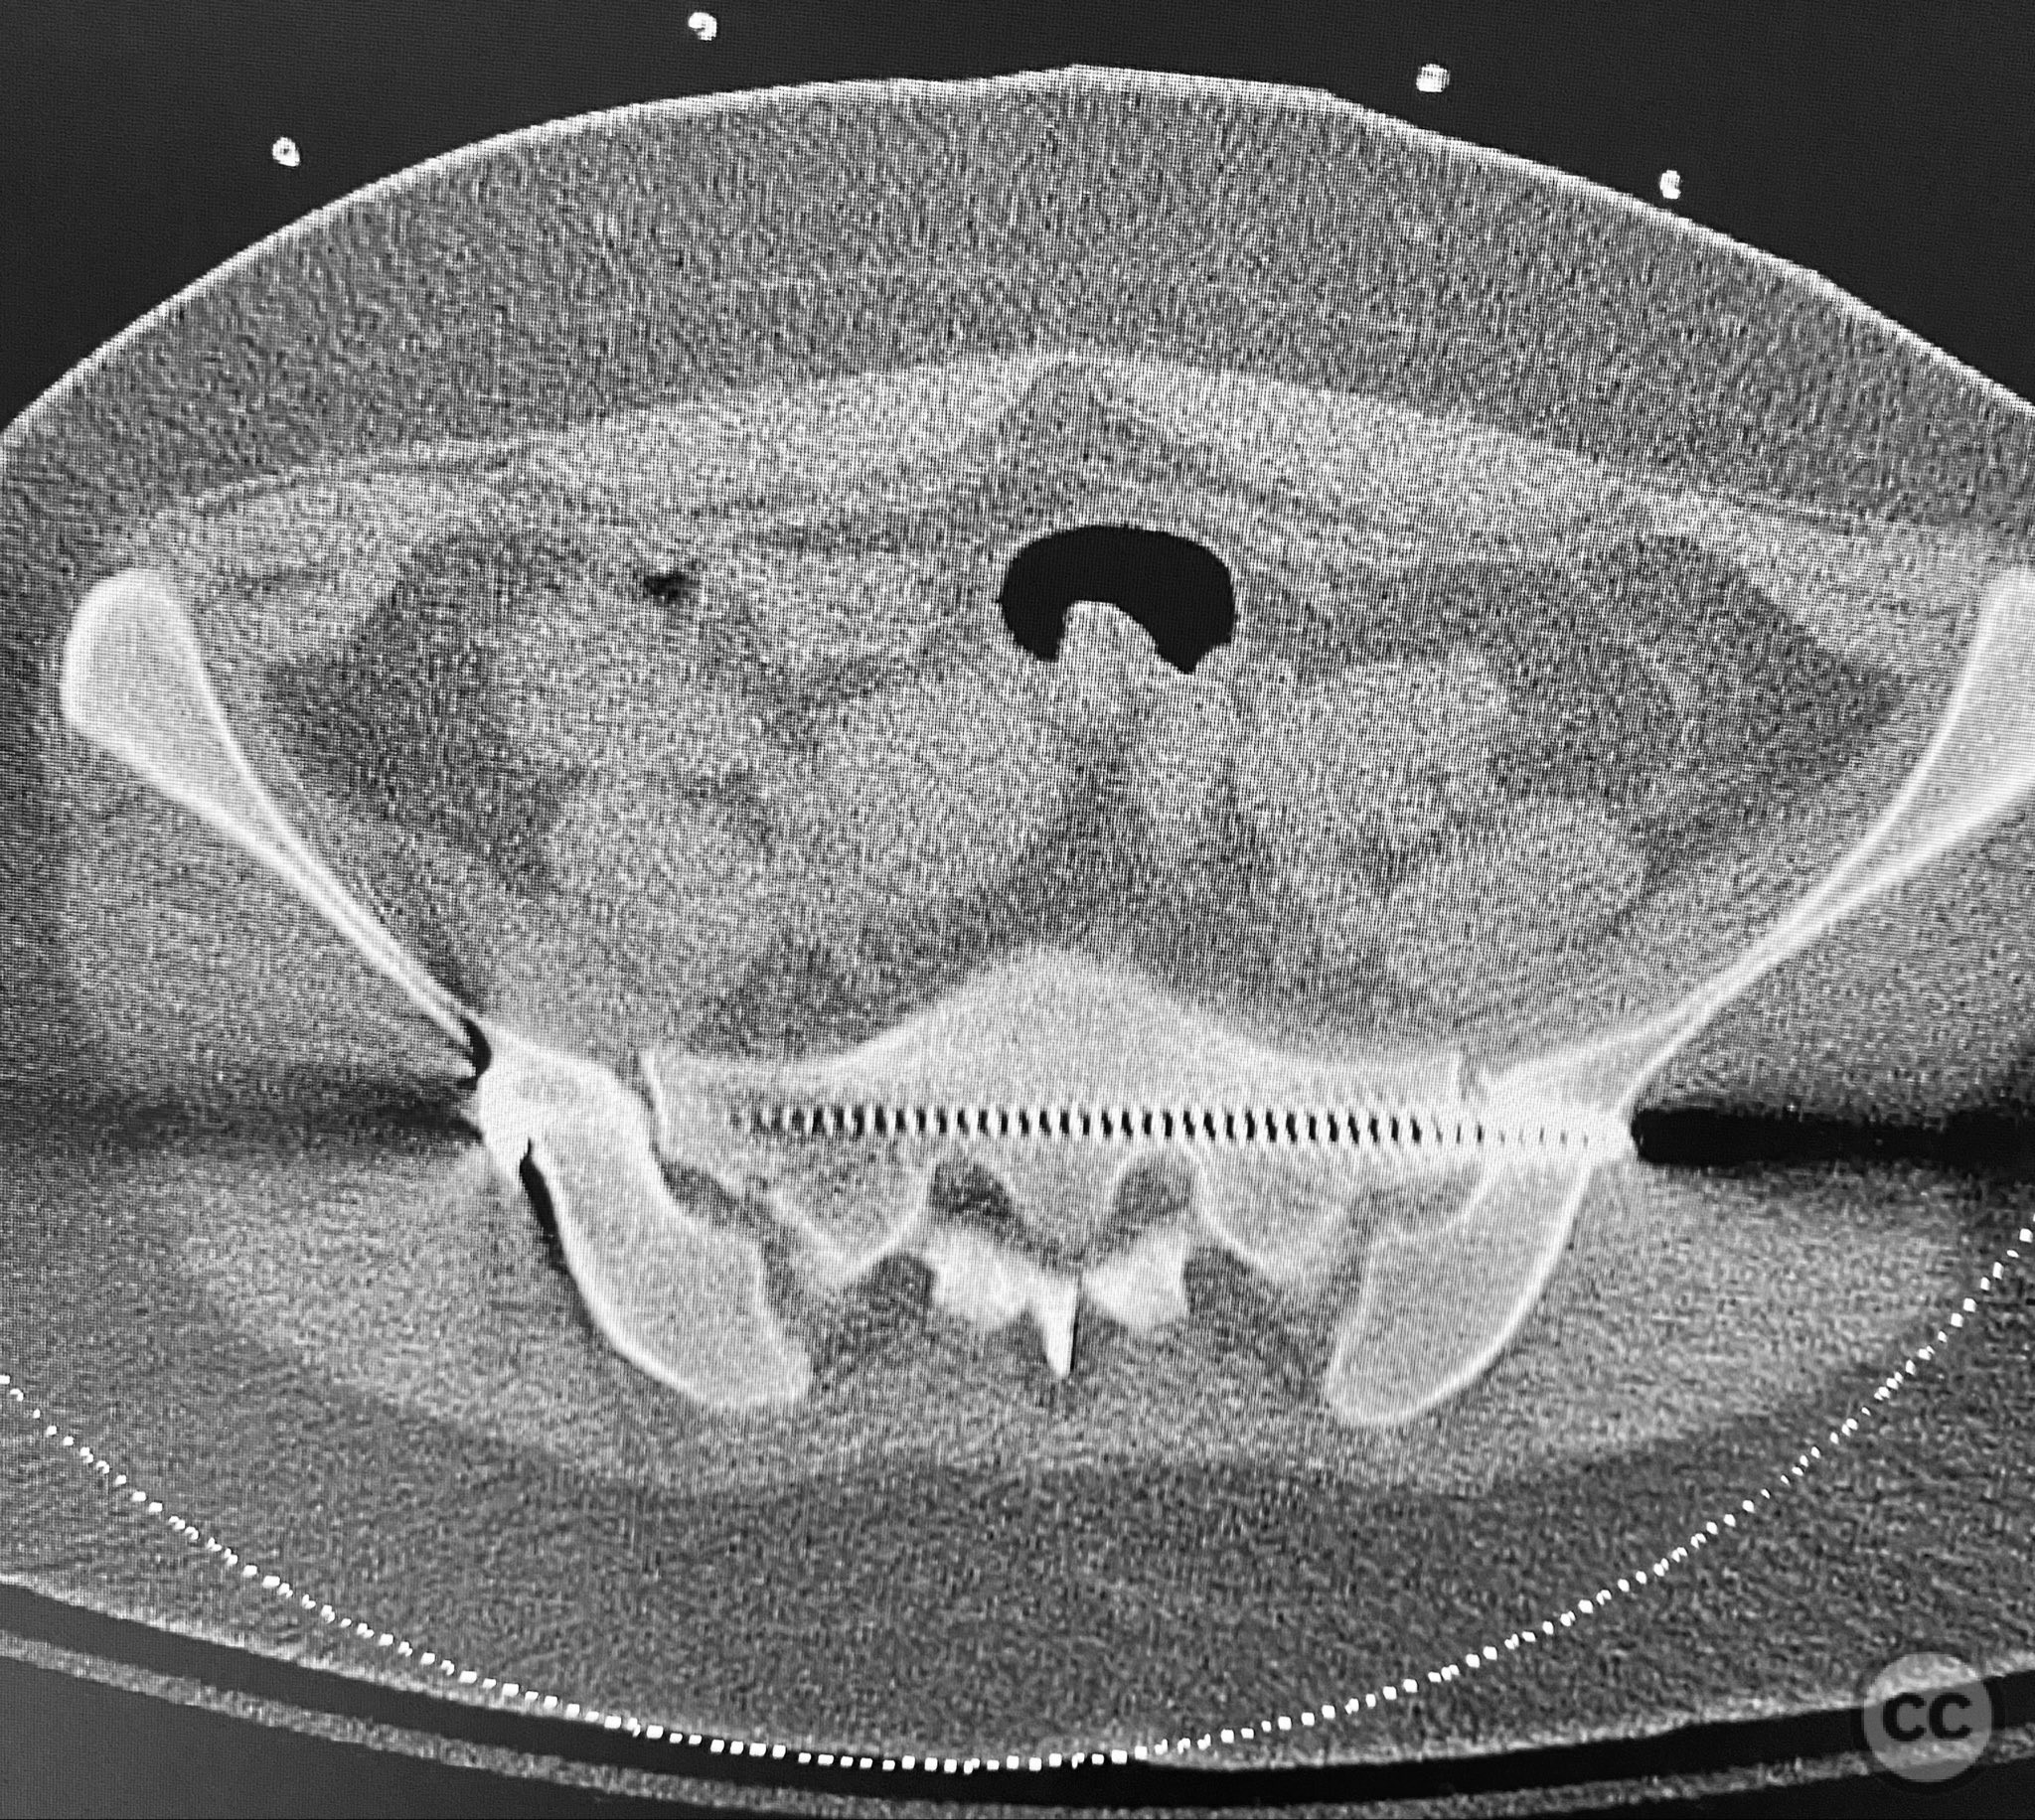

Clinical and radiological findings:  A young adult female sustained a high-energy pelvic injury following a motorcycle crash. She was hemodynamically stable on presentation, with normal neurovascular examination and no evidence of genitourinary, vaginal, or rectal injury. She reported pain localized to both anterior and posterior pelvic regions. Initial plain radiographs (with and without pelvic binder) demonstrated multiple anterior ring fractures and dislocations. The binder images obscured the full extent of injury. Further intraoperative fluoroscopic imaging (AP, inlet, and with lower extremities in "lotus" position) revealed bilateral sacroiliac (SI) joint disruptions (right greater than left), bilateral superior/inferior pubic ramus fractures (right greater than left), and symphyseal diastasis. Notably, the right pubic ramus demonstrated excessive curvature, complicating potential percutaneous screw fixation. AO/OTA classification: 61-C1.3 (bilateral complete disruption of the posterior arch with associated anterior ring injury). Young-Burgess classification: APC III.

Patient positioning:  The patient was positioned supine on a radiolucent operating table under general anesthesia. For intraoperative assessment, the lower extremities were placed in a "lotus" position to enhance visualization of pelvic ring injuries under fluoroscopy.

Intraoperative fluoroscopy with AP and inlet views, as well as dynamic positioning of the lower extremities, was critical in fully delineating the extent of injury, which had been underestimated on preoperative imaging due to binder application. The excessively curved morphology of the right pubic ramus precluded safe or effective straight screw fixation; therefore, ORIF with a contoured plate was performed using intrapelvic exposure for optimal fit and stability. Indirect closed reduction of the SI joints was accepted, followed by percutaneous trans-sacral screw fixation under fluoroscopic guidance. This case highlights the necessity of thorough intraoperative assessment for occult or underestimated injury patterns in complex pelvic trauma, particularly when initial imaging is performed with a pelvic binder in situ.